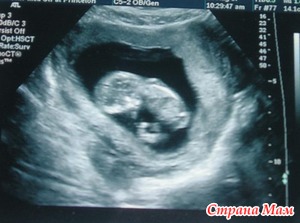

Сходила вчера на первое плановое УЗИ, в дневнике можете подробнее почитать, а тут выложу свою принцессу (доктор сказал что 70% что будет девочка, а я верю этому доктору

УЗИ - класс!!!! Такая она большая у тебя вымахала!!!! И красотуля!!!